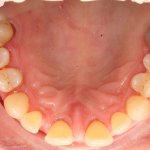

Algseis:

Kaugelearenenud parodontiit, liikuvad hambad, sügavad 6-8 mm igemetaskud, veritsevad igemed.

Pildid enne: